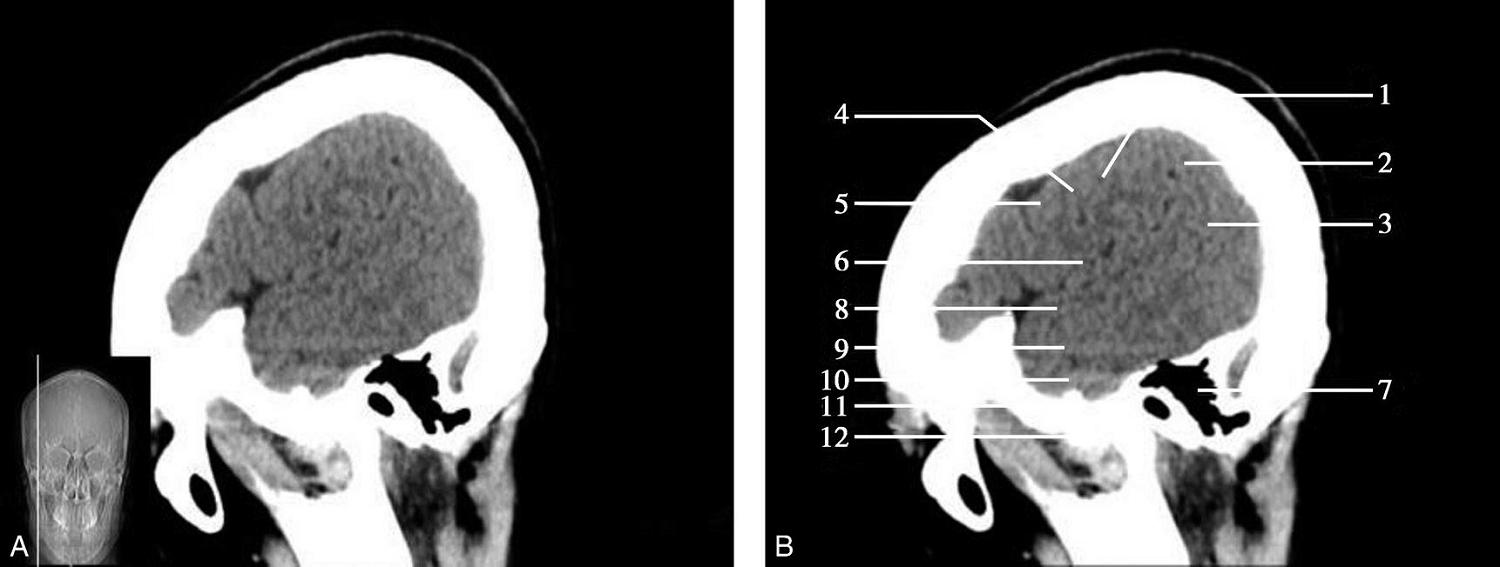

重要结构:胼胝体、垂体、中脑导水管、扣带回、中央沟、第三脑室、斜坡(图1-2-59、图1-2-60)。

图1-2-59 正中矢状面CT

A.矢状面;B.矢状面标注

1.中央沟;2.扣带回;3.胼胝体体部;4.侧脑室;5.中脑;6.胼胝体膝部;7.穹隆;8.第三脑室;9.胼胝体压部;10.垂体;11.中脑导水管;12.第四脑室;13.脑桥;14.蝶窦;15.斜坡;16.小脑扁桃体;17.延髓

此层面可显示胼胝体全貌,它位于层面中央区域,是呈上凸下凹的弧形结构,由前向后分为嘴、膝、体和压四部分。扣带回环绕胼胝体上方,扣带沟位于扣带回的上方。大脑半球中部和后部分别可见较深且恒定的中央沟和顶枕沟。中央沟为是额叶顶叶分界标志。

胼胝体下方为侧脑室及穹窿,第三脑室借穹窿与前上方的侧脑室体部分开,背侧丘脑的内侧面以及中脑顶盖分别为第三脑室的外侧壁和底。第三脑室向前籍室间孔与侧脑室相通,向下经中脑导水管通第四脑室。中脑腔狭窄呈管状,即称为中脑导水管,中脑导水管畸形,常见者为导水管的分叉畸形和狭窄,其次可见中脑导水管膈膜,造成先天性脑积水。

脑干由中脑、脑桥和延髓组成,自第三脑室底向下后稍斜行,移行于颈髓。由上至下,脑干腹侧可见脚间池、桥前池和延髓池,脑干背侧可见大脑大静脉池、四叠体池和小脑延髓池。

垂体位于蝶鞍内,其前部为腺垂体,后上部分为神经垂体。垂体下方为鞍底及蝶窦,上缘因鞍膈存在而平直,垂体借垂体柄向上连于丘脑下部。垂体的前上方见视交叉和视束。斜坡作为前颅窝底的重要组成部分与多个重要结构相比邻,矢状位呈三角形,颅内肿瘤或颅外鼻咽部恶性肿瘤均可侵犯至此,原发肿瘤常见为脊索瘤。小脑幕居枕叶和小脑之间,向后下连接窦汇,向前至中脑后方游离,称小脑幕切迹。小脑幕下方为小脑扁桃体。成年人小脑扁桃体下缘由枕骨大孔向下疝入椎管超过5mm称为Chiari畸形,以矢状位显示最佳。